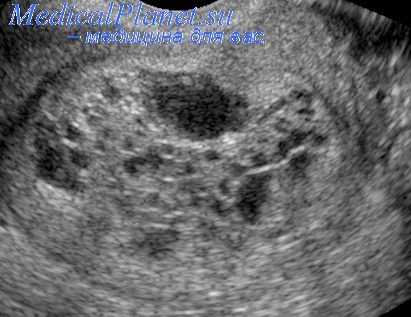

УЗИ при пузырном заносе

В дальнейшем пациентка находится под постоянным наблюдением, и образцы ее крови и/или мочи регулярно отсылаются в центр для анализа. При периодическом обследовании проводится анализ крови на b-ХГЧ, КТ грудной и брюшной полости. Полезным оказывается УЗИ газовой области.

- Лучевые методы. Посредством УЗИ органов малого таза выявляется увеличение матки, наличие в матке мелкокистозной ткани, двусторонние текалютеиновые кисты. Опухолевый узел хорионкарциномы может иметь размеры от нескольких сантиметров до размеров головы взрослого человека. С уточняющей целью применяется гистерография – рентгеновское исследование матки.